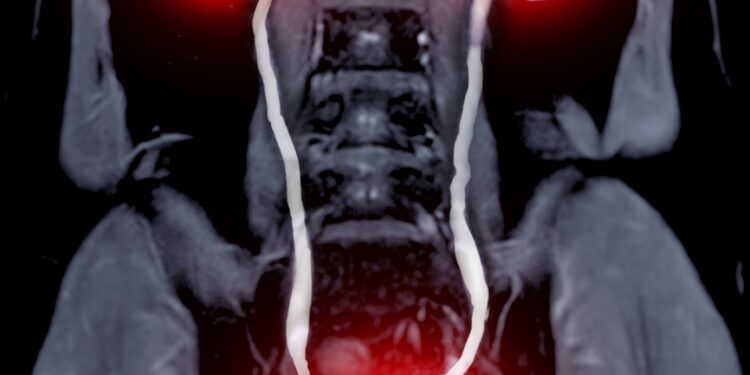

Kovas – tai mėnuo, kai ypač daug dėmesio skiriama inkstų vėžio žinomumo didinimui. Jei šia liga serga jūsų artimieji ar patys esate susidūrę su diagnoze, šis laikotarpis – puiki proga ne tik daugiau sužinoti apie inkstų sveikatą, bet ir skatinti kitus pasirūpinti savimi.

Inkstų vėžys – viena dažniausių onkologinių ligų, paveikianti tiek vyrus, tiek moteris. Nors dažnai liga būna nebyli, ankstyva patikra ir informacijos sklaida gali turėti lemiamos įtakos sveikatai ir gydymo sėkmei. Kovas suteikia galimybę ne tik išreikšti palaikymą sergantiesiems, bet ir dalyvauti prevencinėse iniciatyvose.

Kai kuriems žmonėms inkstų vėžio tikimybė didesnė. Riziką padidina tokie veiksniai kaip rūkymas, padidėjęs kraujospūdis, antsvoris ar inkstų vėžio atvejai šeimoje. Net jei jaučiatės gerai, verta atlikti inkstų patikrą – ypač jei priklausote rizikos grupei.